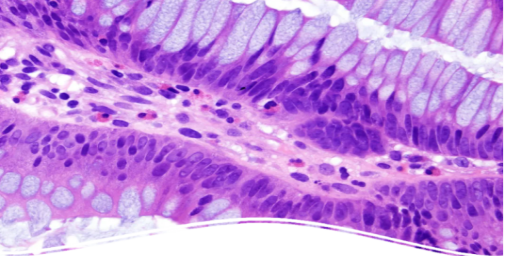

蘇木精—伊紅染色法(Hematoxylin-eosin Staining),簡稱HE染色法,是組織學(xué)、胚胎學(xué)、病理學(xué)教學(xué)與科研中最基本、使用最廣泛的技術(shù)方法。

蘇木精染液為堿性,主要使細(xì)胞核內(nèi)的染色質(zhì)與胞質(zhì)內(nèi)的核糖體著紫藍(lán)色;伊紅為酸性染料,主要使細(xì)胞質(zhì)和細(xì)胞外基質(zhì)中的成分著紅色。

使用小鼠腦(海馬)標(biāo)本進(jìn)行HE染色時

使用deColorizing Solution 1進(jìn)行脫色

紅色:Iba1,藍(lán)色:DAPI